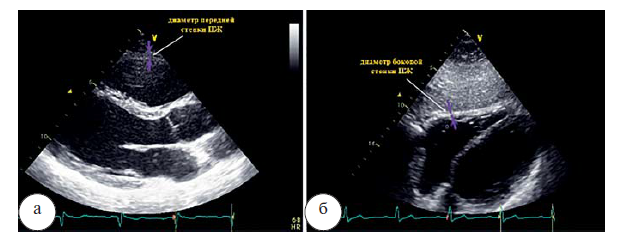

Проксимальный диаметр выходного тракта (ВТПЖ) должен быть измерен в продольном парастернальном сечении по длинной и короткой оси в конце диастолы. Верхняя граница составляет 36 мм (рис. 2 а, б). Дистальный диаметр ВТПЖ, измеренный в конце диастолы на уровне пульмонального клапана должен составлять менее 28 мм (рис. 2 в).

Рис. 2. Измерение проксимального диаметра выходного тракта ПЖ в парастернальном сечении по длинной оси (а), по короткой оси (б), дистального диаметра выходного тракта ПЖ в парастернальном сечении на уровне пульмонального клапана (в)